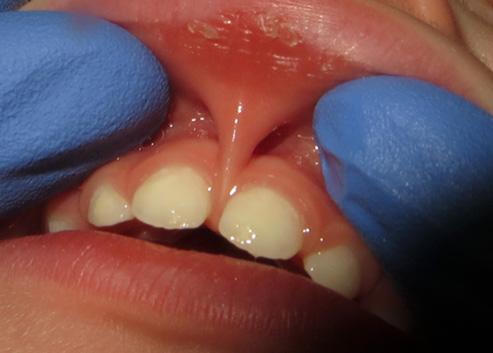

A tongue-tie (ankyloglossia) is a movement restriction of the tongue caused by an excessively tight thin tissue (frenum) connecting the tongue and the floor of the mouth. Equally, a lip-tie occurs when the tissue between the upper lip and the gums does not allow the lips to move freely, and a cheek-tie influences the movement and functioning of the cheeks.